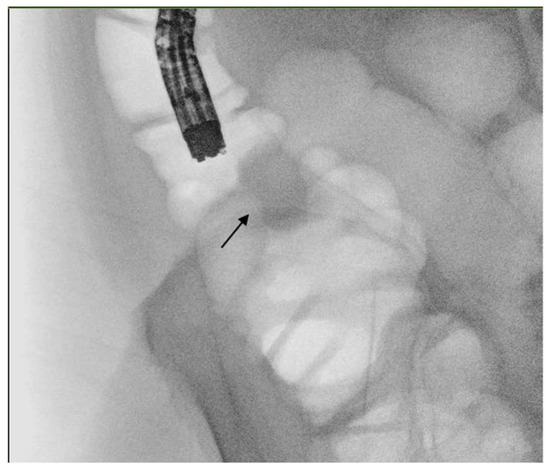

5.2. Technique

5.3. Procedural Adverse Events and Post Endoscopic Management